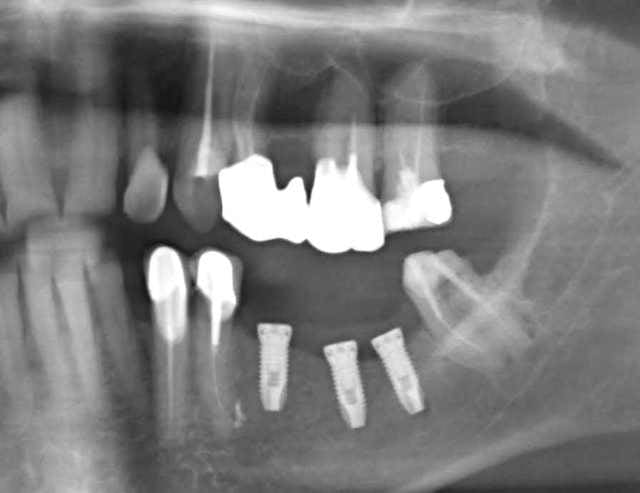

Grossière erreur lors des sutures et exposition de l'os et des implants, malgré tout on continue car belle gencive kératinisée après cicatrisation de ce bordel et résultat au bout de 2 ans ... (entre temps 38 a été virée)